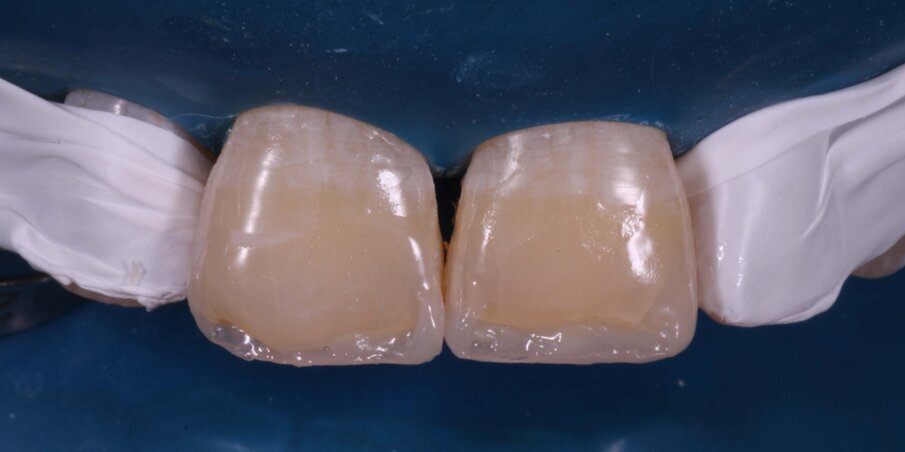

Enamel Shade A3 of a nanocomposite (FiltekZ350XT,3M) was adapted on the previously scored putty index, placed in position and light-cured for 20 seconds. This gave us the palatal shell on which we layered the Dentin and Body Shades (A3) sequentially (Fig 10 -12). Proximal walls were created with enamel shade composite and thin mylar strips with a palatal pull-through technique. A thin final layer of enamel shade was applied and photocured (Fig 13-14).

Fig 10: Building proximal walls in enamel shade composite after creating the palatal enamel shell

Fig 11: First layer of Dentin Shade Composite

Fig 12: Second layer of Body Shade composite

Fig 13: Final layer of Enamel Shade composite covering the entire bevel